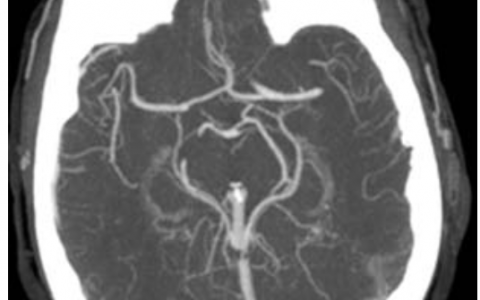

A 55-year-old man with hypertension is pre- scribed an antiarrhythmic agent that alters the flow of cations in myocardial tissue. The image is a trace of a myocardial action potential. Each phase is associated with the opening and/ or closing of various ion channels. Which of the following would be affected by an agent that affects phase 0 of the myocardial action potential?

1例55岁男性高血压患者,预先接受了改变心肌组织中阳离子流动的抗心律失常药物。图像是心肌动作电位的痕迹。各相与各种离子通道的开放和(或)关闭有关。影响心肌动作电位0相的药物会影响以下哪一项?